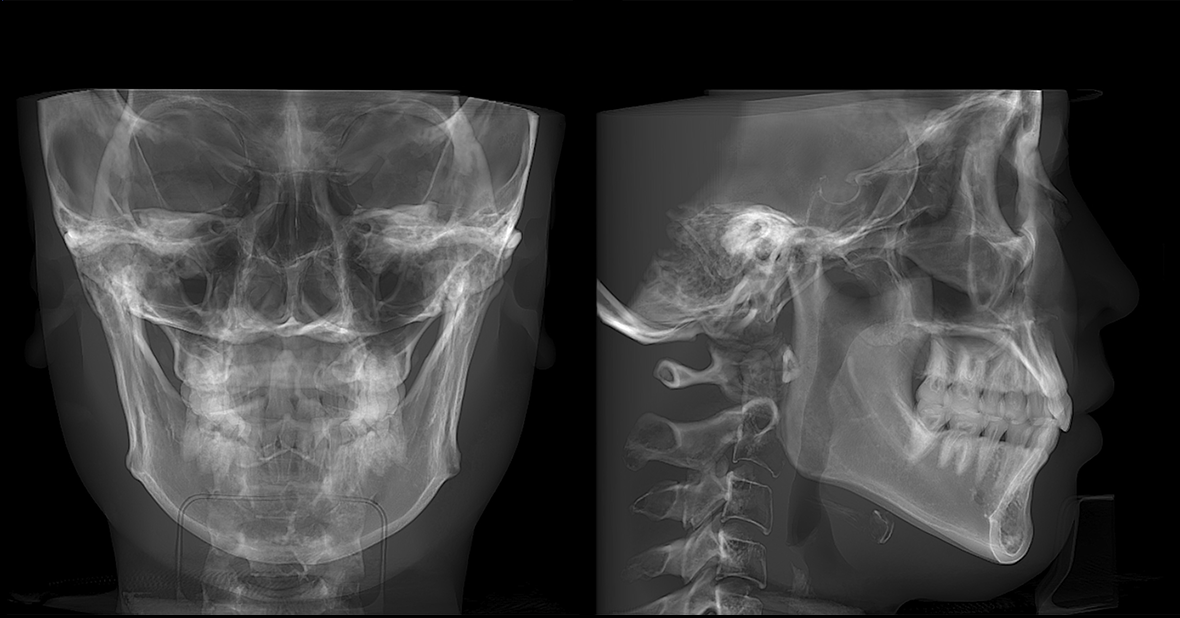

• lamtau AI头影测量

AI头影测量

单侧头影测量 专利 首创

偏颌患者的侧位片左右侧的影像不对称,实际正畸测量时会产生较大的误差。有方医疗推出单侧头影测量功能。这一功能有效解决了这一临床问题,在口腔正畸领域广受好评,并于2023年成功获得国家发明专利授权。